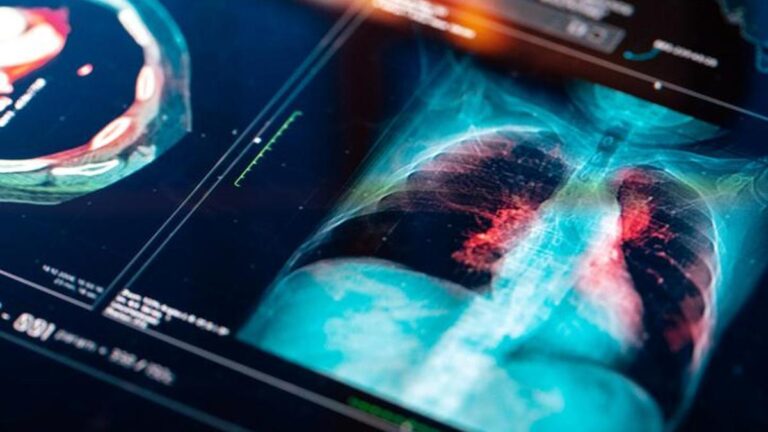

Akciğer kanserini anlamak için semptomlar ilk kez tartışılır. Bu semptomlar, kişiden başlayarak uzman doktorun kontrolü altındaki ön muayene ile sağlanır. Zayıflık, yorgunluk, öksürük anında kanı, kilo kaybı ve iştah kaybı gibi birçok semptom ön plana çıkar. Bu işlemin ardından, prosedür görüntüleme yöntemleri göz önüne alındığında kesin tanı için uygulanır.

Bu nedenle, düşük dozaj akciğer tomografisinin bu anlamda önemli bir yeri vardır. Özellikle erken tomografi ile gerekli tedavi yöntemleri daha etkili olabilir. Ek olarak, kan testleri ve açıklık testleri de pulmoner kanser açısından tartışılmaktadır. Bu nedenle, gerekli tanılarda tartışılan yöntemler birden fazla şekilde kullanılır ve sonuç dahil edilir.